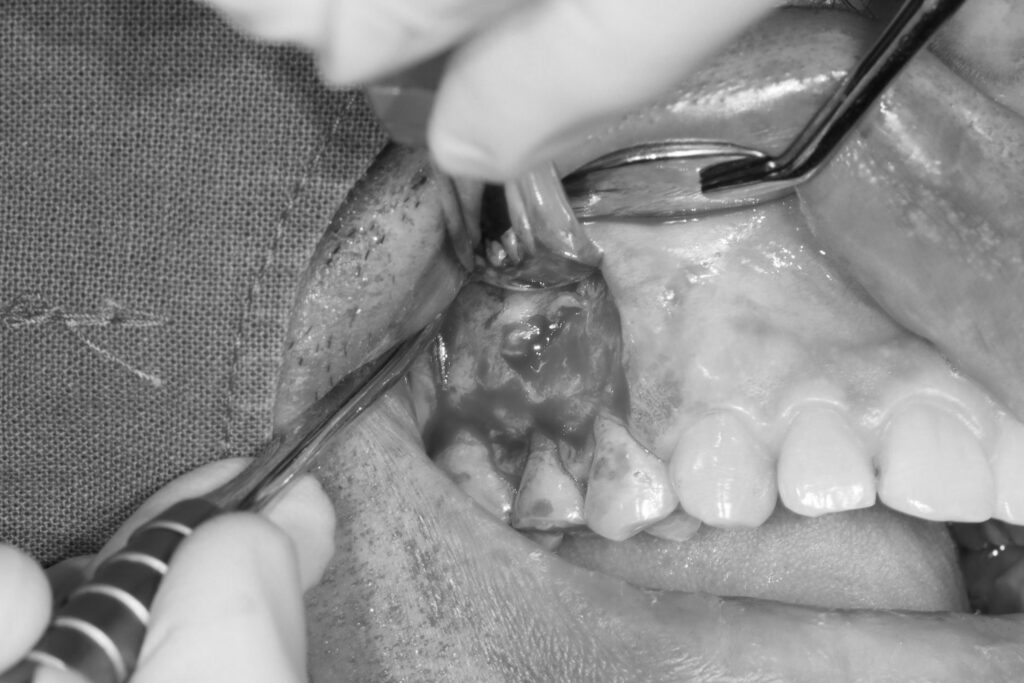

이후 치근단 절제술을 시행하였는데요.

사이즈가 너무 크다 보니 보통은 잘 하지 않지만

뼈이식을 함께 진행하였습니다.

치근단절제술은 치아 뿌리 끝에 생긴

염증이나 낭종을 외과적으로 제거하는 수술로

보통 신경치료를 받은 후에도 뿌리 끝 주변 조직에

세균이 침투하거나 치근관의 해부학적 구조가 복잡해

약물이 끝까지 도달하지 못할 때 시행됩니다.

재신경치료로 해결되지 않는 경우에 한해

치아의 뿌리 끝을 절제해 염증 부위를

직접 정리함으로써 통증과 감염을 차단하는 것이 목적입니다.